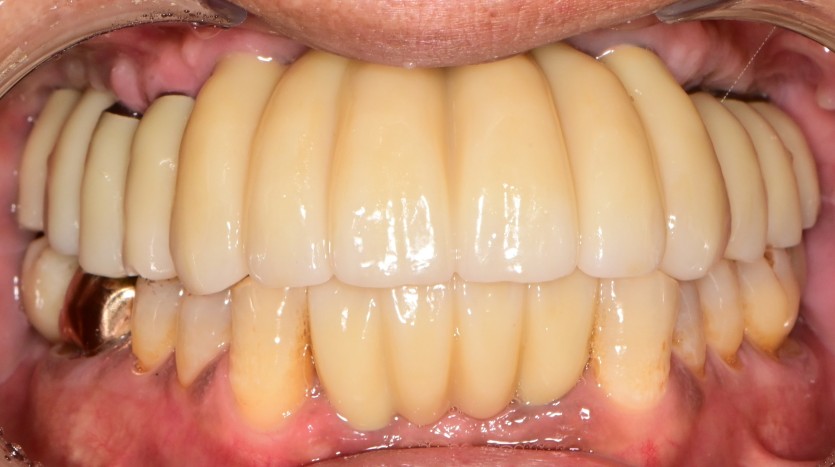

만 65세 상악 전체 임플란트 증례 (하악 전치부)

상악 전체 임플란트 증례입니다.(하악 전치부)

12개의 임플란트로 완성하였습니다.